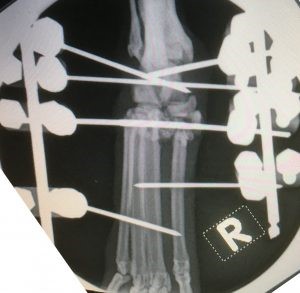

Stabilisation involved the placement of type 2 external fixator. This stayed on for 3.5 months before removal.